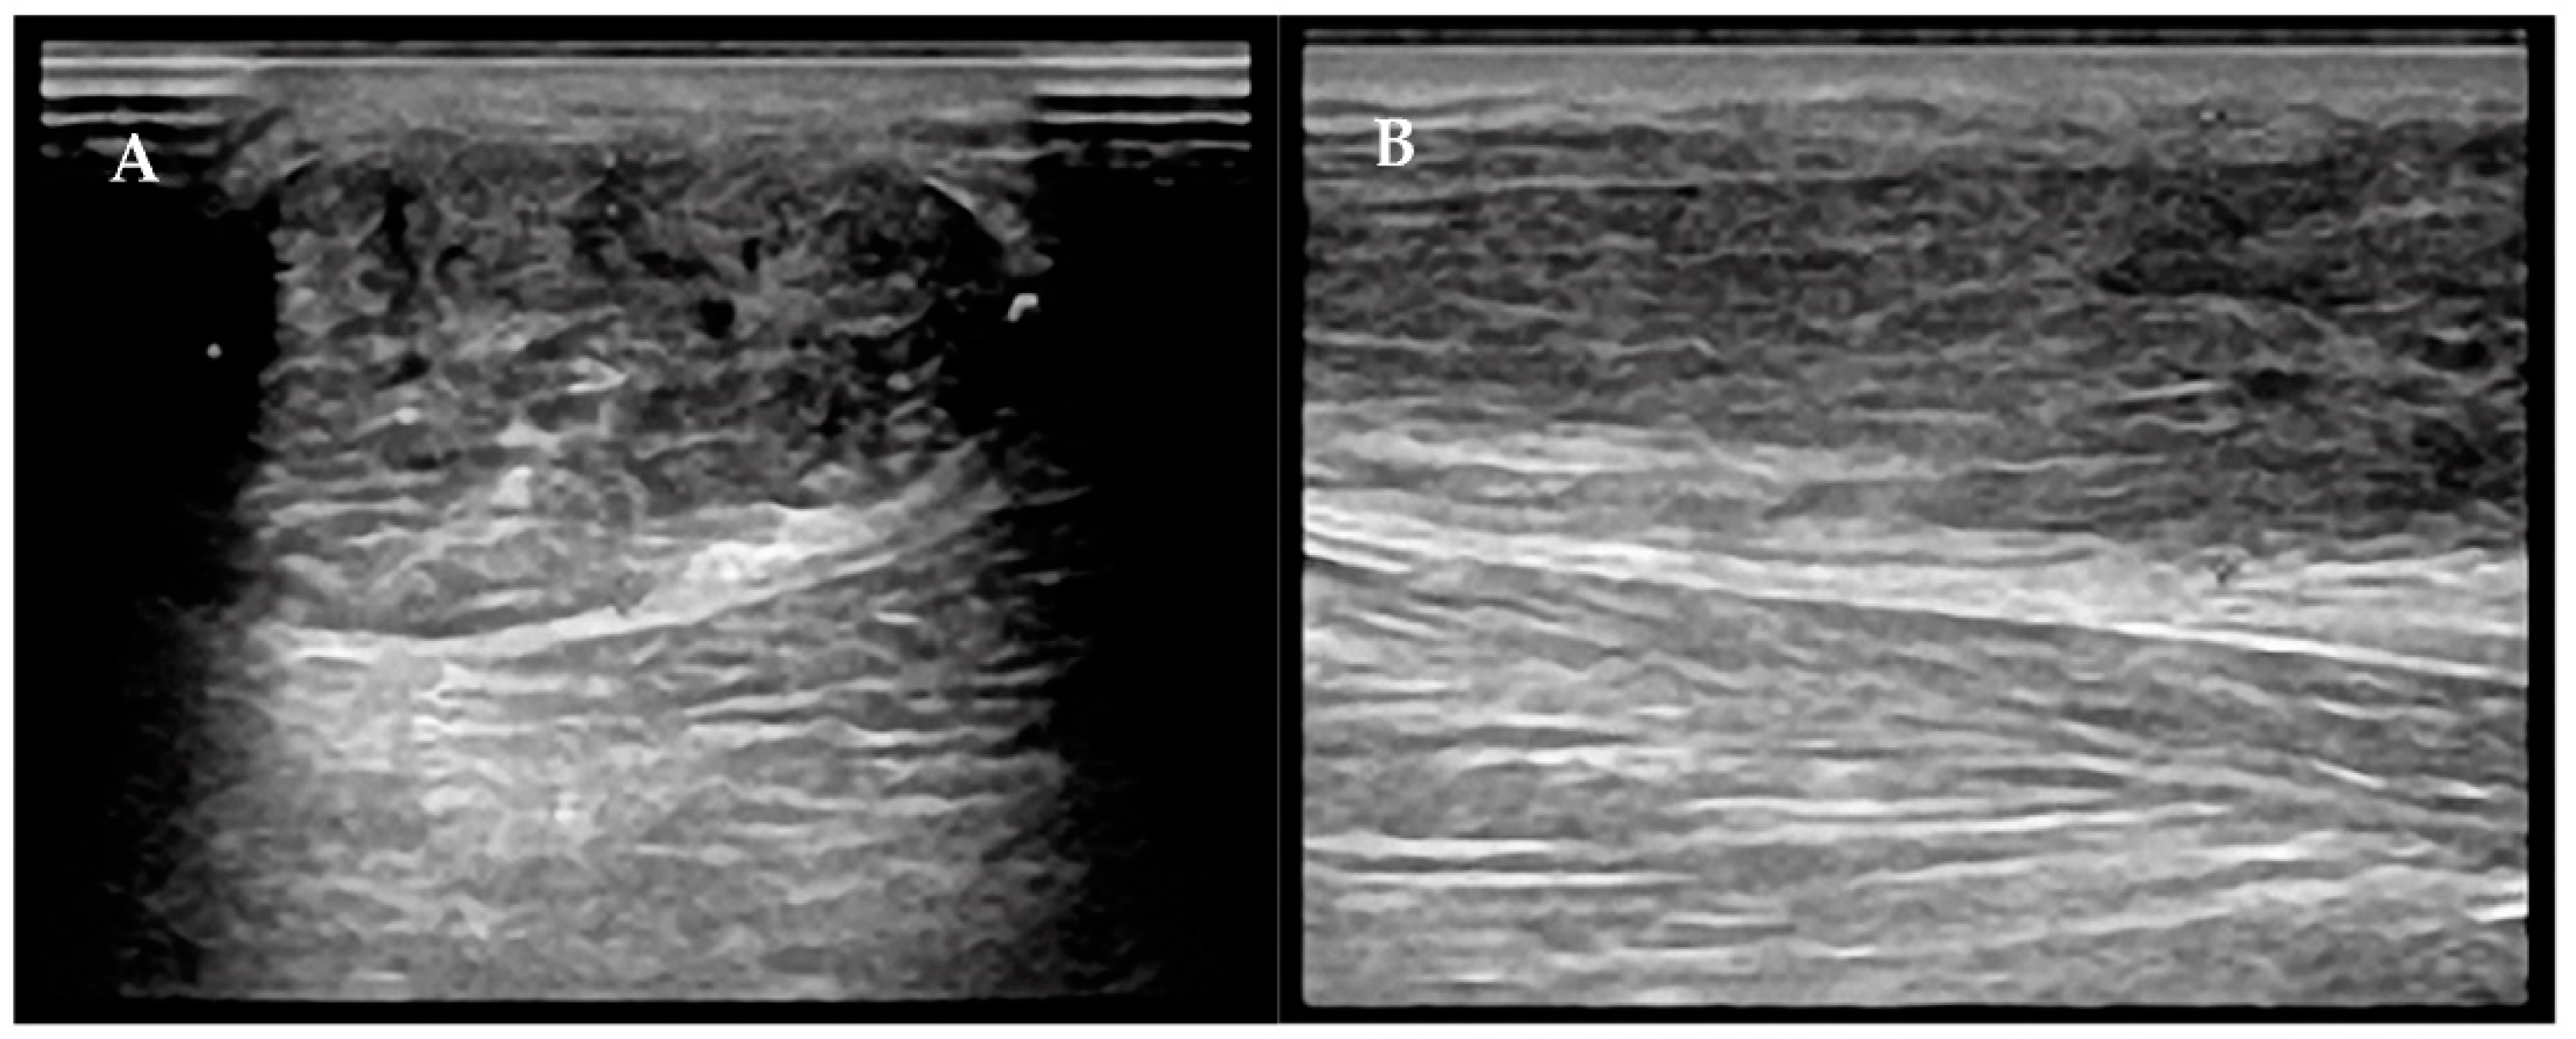

- Gitto, S.; Draghi, A.G.; Bortolotto, C.; Draghi, F. Sonography of the Achilles Tendon After Complete Rupture Repair: What the Radiologist Should Know. J. Ultrasound Med. Off. J. Am. Inst. Ultrasound Med. 2016, 35, 2529–2536. [Google Scholar] [CrossRef] [PubMed]

- Busilacchi, A.; Olivieri, M.; Ulisse, S.; Gesuita, R.; Skrami, E.; Lording, T.; Fusini, F.; Gigante, A. Real-Time Sonoelastography as Novel Follow-up Method in Achilles Tendon Surgery. Knee Surg. Sports Traumatol. Arthrosc. Off. J. ESSKA 2016, 24, 2124–2132. [Google Scholar] [CrossRef]

- Cohen, M. US Imaging in Operated Tendons. J. Ultrasound 2012, 15, 69–75. [Google Scholar] [CrossRef]